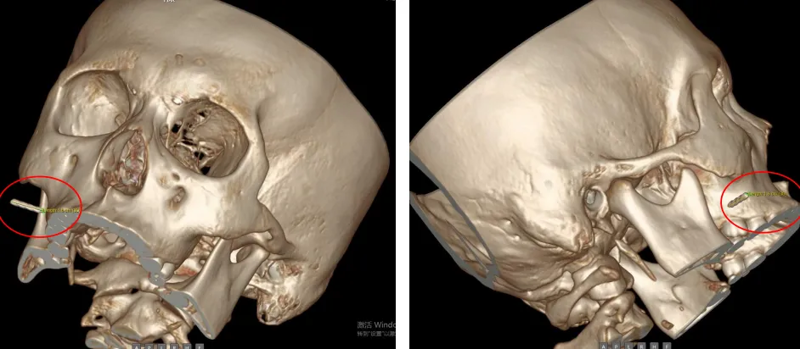

接诊医生唐亮主任医师为患者进行详细检查,发现患者面部多发红色丘疹、皮肤硬结及白色脓疱状丘疹,双颊、颏部有明显色素沉着,右侧面颊局部红肿、触痛明显,但体表未触及明确异物。结合患者病史及症状,医生判断,断针残留已引发明显的面部软组织炎症反应,若不及时取出,断针可能进一步移位,损伤面部神经、血管或腮腺等重要组织,后果不堪设想。同时,患者及家属明确提出美容取针需求,希望尽可能减少面部疤痕。为精准定位断针位置,耳鼻咽喉头颈外科团队为患者进行CT三维重建检查,结果显示,一枚长约1.6cm的断针深埋于患者面部软组织内。针对患者情况,科室迅速组织术前讨论,联合手术麻醉中心等相关科室团队制定个性化治疗方案,最终决定在气管插管全麻下,借助C臂X光机引导,经口实施手术取异物,并同步开展右颌面部修复处理,既确保断针完整取出,又最大限度兼顾面部美观。

手术过程充满挑战,由于患者面部炎症明显、软组织肿胀,断针暴露差,给寻找和取出工作带来难度。术中,手术团队在C臂X光机的精准引导下,通过经口右侧颊部近后磨牙处约2cm的切口逐步探查,凭借精湛的显微操作技术,用显微组织钳多次调整角度,缓慢接近异物,最终在眼科异物磁吸器的协助下,于腮腺内前方成功找到断针,并将这枚长约1.6cm的断针完整取出。术后检查确认,患者脸部无异物残留、无组织锈迹及活动性出血,也未造成腮腺组织损伤。